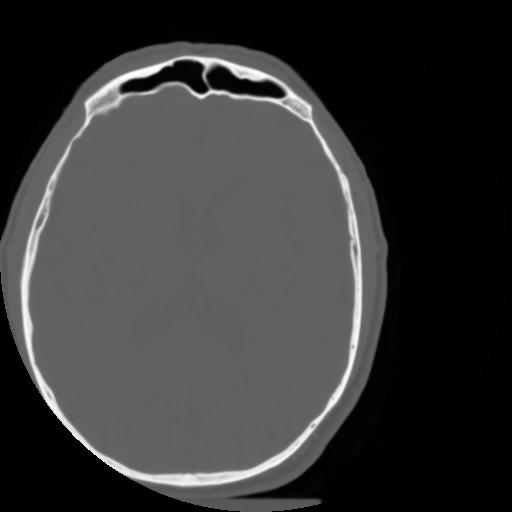

3 CEREBRO,,Axial,3.0,CEREBRO,,